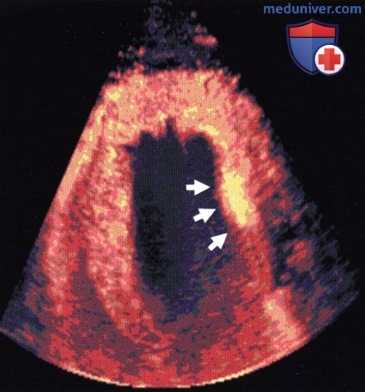

![Перспективы применения контрастной эхокардиографии]()

Маркировка статичных лейкоцитов в сердце свиньи через 20 мин после инъекции. Контрастное средство обнаруживается только в миокарде (стрелки: очаг постишемического воспаления).